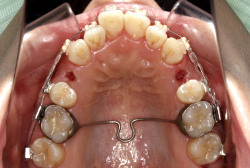

ネックバンドを1年半使用して、上顎大臼歯が十分後ろに下がったところで、裏側にリンガルアーチという固定のワイヤーを取り付けて、新しく生じた隙間が狭くならないよう「保隙(ほげき)」という処置をして、永久歯が生えそろうまで待機中の様子です。配列全体に隙間が生じているのがお分かりいただけると思います。これだけの隙間が確保できていれば、抜歯をしなくても、あとで上の前歯を内側に理想的な角度で引っ込めることができます。このように完全に永久歯列になる前に、十分な隙間が確保できるかどうかが、非抜歯で矯正できるかどうかの分かれ目になります。

初診時と違い、上の奥歯がより後方に下がっていることが分かります。ただしこの段階では奥歯は後ろに下がりすぎの状態です。しかし次の段階でマルチブラケット法を始めると、上の奥歯は次第に前にズレて来ます。最終段階で正しい位置にするためには、この段階では余分に後ろに下がっている必要があります。